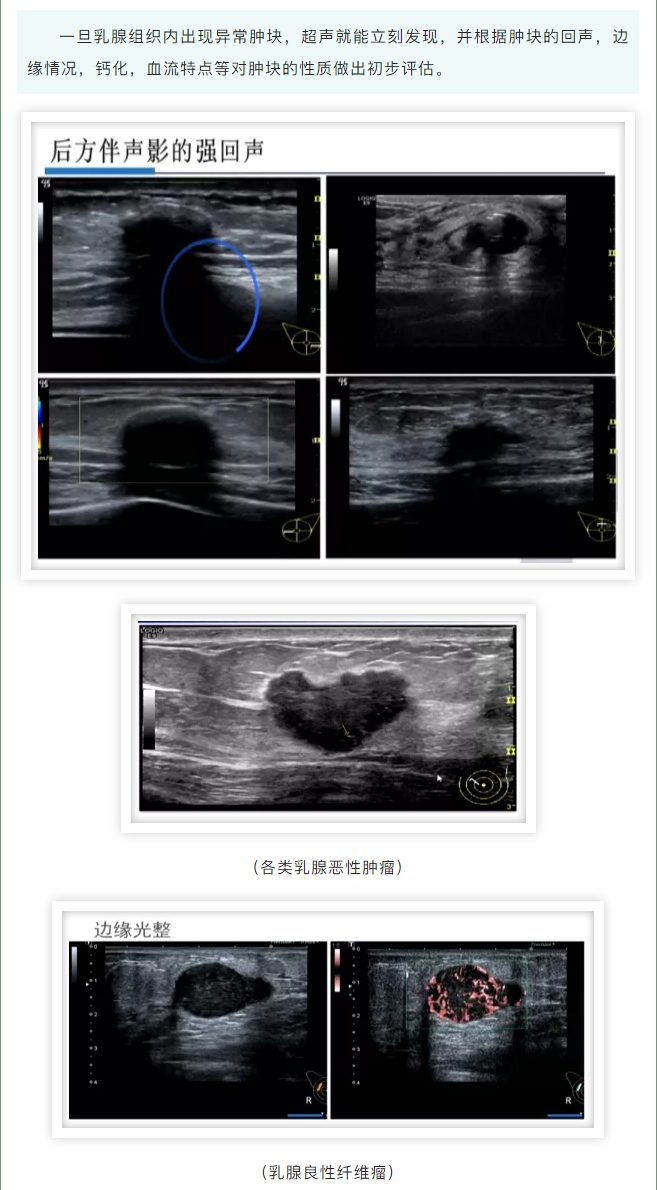

发现乳腺肿块,它俩帮了大忙!_01.jpg

发现乳腺肿块,它俩帮了大忙!_02.jpg

发现乳腺肿块,它俩帮了大忙!_03.jpg

发现乳腺肿块,它俩帮了大忙!_04.jpg

发现乳腺肿块,它俩帮了大忙!_05.jpg